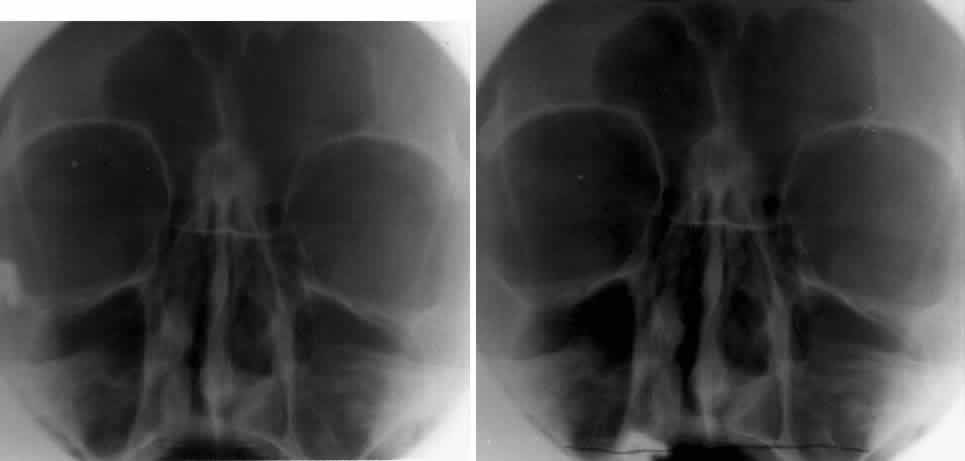

CALDWELL PROJECTION

In 1918 the evaluation of the frontal and ethmoid sinuses prompted Caldwell9 to describe a projection (Fig. 3) that eliminates the superimposition of the sphenoid bone on these paranasal sinuses. The patient is positioned with both the nose and forehead against the x-ray cassette while the x-ray beam is directed downward 15 degrees to 23 degrees to the canthomeatal line.5,6,9 This orientation also projects the petrous bones inferior to the orbit, thus avoiding obscuration of the orbital structures. As in the Waters view, the Caldwell view is a posterior-anterior projection. This excellent view of the frontal and ethmoid sinuses also allows good visualization of the orbital rims, greater and lesser sphenoid wings, lacrimal gland fossa, medial orbital wall, and both the superior and inferior orbital fissures.10 The innominate line is prominent in this view and represents the depression on the temporal surface of the greater wing of the sphenoid bone where it forms the medial wall of the temporal fossa or lateral wall of the orbit. This innominate line can be straight, end with a medial right angle turn, or continue inferiorly to form the outline of the pterygoid plate.8 A lack of continuity of the innominate line suggests a fracture of the lateral orbital wall.

Fig. 3. A. Schematic showing positioning for a Caldwell projection. (CM, canthomeatal line; CR, central ray) B. Radiograph of a Caldwell projection. The petrous ridge is positioned at the orbital floor. Detail of the orbital floor and maxillary sinus is blocked. C. The radiograph is taken at a steeper angle so the petrous ridge is now positioned lower within the maxillary antrum. (a, frontal sinus; b, innominate line; c, inferior orbital rim; d, posterior orbital floor; e, superior orbital fissure; f, greater wing of sphenoid;g, ethmoid sinus; h, medial orbital wall; i, petrous ridge; j, zygomatic-frontal suture; k, foramen rotundum) (A; Rao VM, Gonzalez CF: Plain film radiography and polytomography of the orbit. In Gonzalez CF, Becker MH, Flanagan JC [eds]: Diagnostic Imaging in Ophthalmology, pp 1–7. New York, Springer Verlag, 1986)